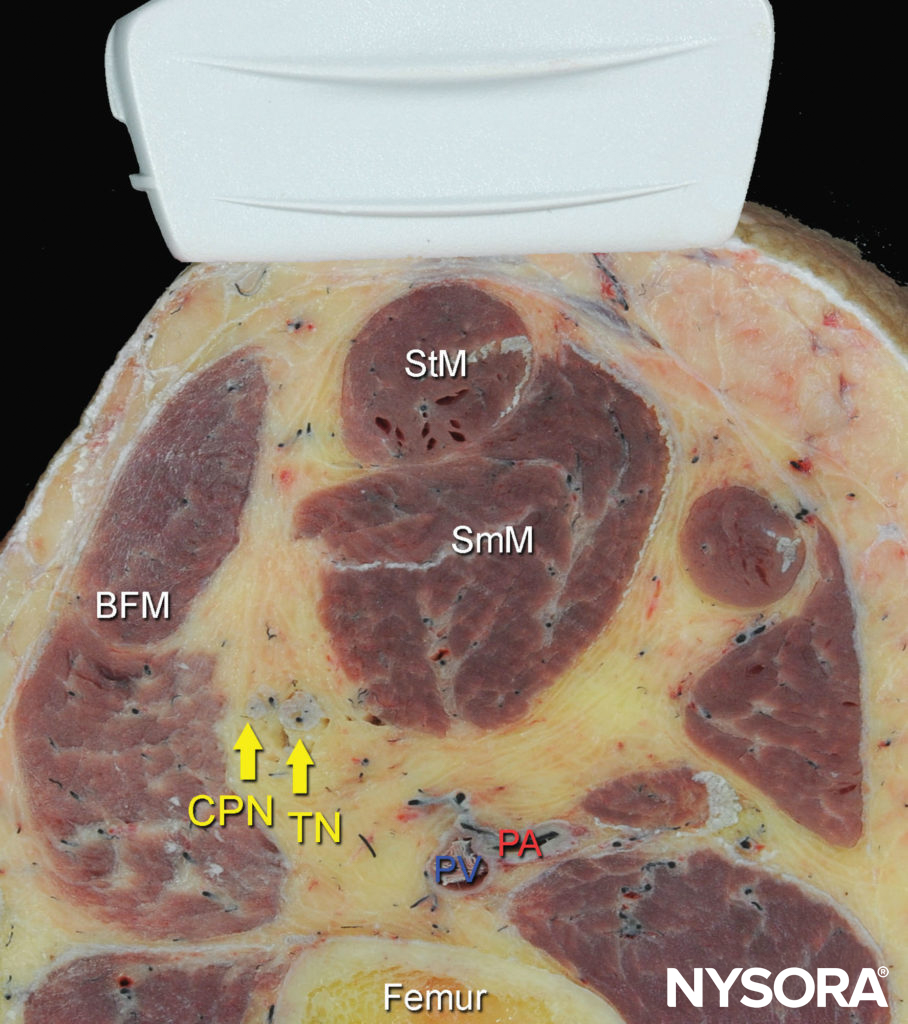

The anatomy of the sciatic nerve in the popliteal fossa is variable, and the division into the tibial nerve (TN) and common peroneal nerve (CPN) occurs at an inconstant distance from the popliteal crease (Figure 1). With nerve stimulator–based techniques, larger volumes (eg, > 40 mL) of local anesthetic have been used to increase the chance of nerve block success.

FIGURE 1. Cross-sectional anatomy of the sciatic nerve in the popliteal fossa. Shown are the common peroneal nerve (CPN), tibial nerve (TN), popliteal artery (PA), popliteal vein (PV), femur, biceps femoris muscle (BFM), semimembranosus muscle (SmM), and semitendinosus (StM) muscle.

Beginning with the transducer in the transverse position at the popliteal crease, the popliteal artery is identified, aided with color Doppler US when necessary, at a depth of approximately 3–4 cm. The popliteal vein accompanies the artery at it is positioned just superficial (posterior) to it. On either side of the artery are the biceps femoris muscles (laterally) and the semimembranosus and semitendinosus muscles (medially). The tibial nerve is positioned superficial and lateral to the vein and is seen as a hyperechoic, oval or round structure with a honeycomb pattern (Figure 3). Asking the patient to dorsiflex and plantar flex the ankle makes the two sciatic nerve branches twist or move in relation to each other. Usually, tilting the transducer caudally is necessary to bring out the nerve from the neighboring adipose tissue.

FIGURE 3. Sonoanatomy of the sciatic nerve at the popliteal fossa. The two main divisions of the sciatic nerve, the tibial nerve (TN) and the common peroneal nerve (CPN), are seen immediately lateral and superficial to the popliteal vein (PV) and artery (PA). This image was taken at 5 cm above the popliteal fossa crease, where the TN and CPN have just started diverging.

Once the tibial nerve has been identified, the CPN is visualized slightly more superficial and lateral to the tibial nerve. The transducer should be slid proximally until the tibial and peroneal nerves are visualized coming together to form the sciatic nerve before its division (Figure 4). This junction usually occurs at a distance 5–10 cm from the popliteal crease but may occur very close to the crease or, less commonly, more proximally in the thigh.

As the transducer is moved proximally, the popliteal vessels move deeper and become more challenging to image. Adjustments in depth, gain, focus, and direction of the US beam should be made to keep the nerve visible at all times. At the popliteal fossa, the sciatic nerve typically is visualized at a depth of 2–4 cm.